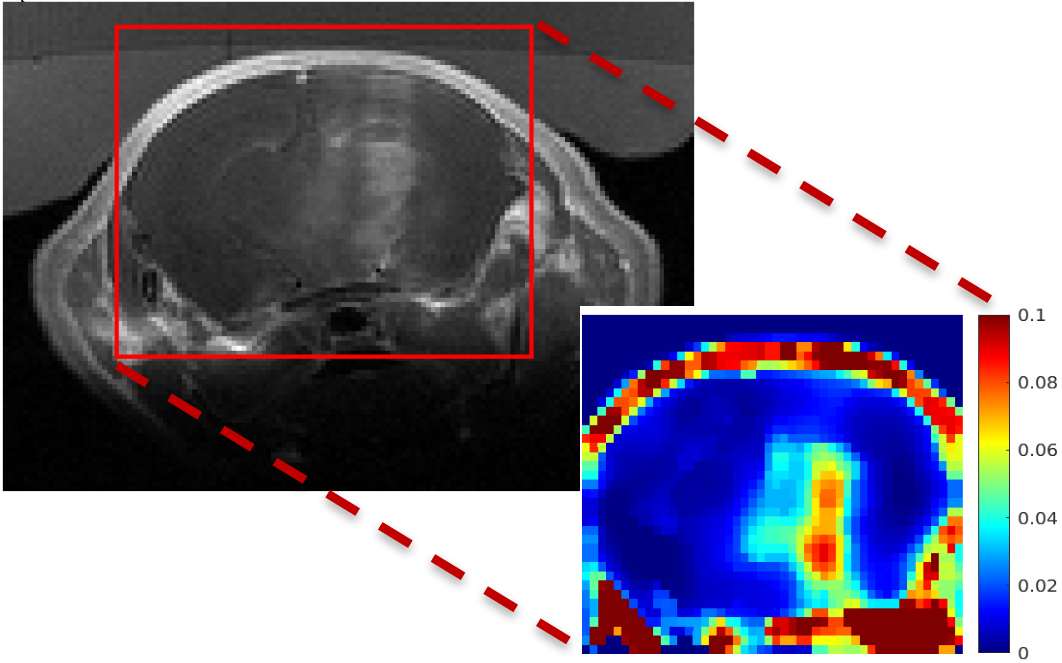

Read more →We have been developing new methods for DCE-MRI perfusion analysis that take the spatial context into account to improve the accuracy of per…

Read more →Imaging myocardium is difficult let alone obtaining quantitative parameters. We developed fast self-gated acquisition based on inversion rec…